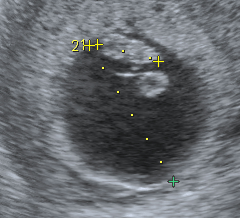

6週照到雙胚囊 但胚囊只有5週大 還沒有囊黃 胚胎 及心跳 Babyhome親子討論區

6週照到雙胚囊 但胚囊只有5週大 還沒有囊黃 胚胎 及心跳 Babyhome親子討論區

5w胎囊幾大 懷孕前後 Baby Kingdom 親子王國香港討論區

孕早期孕囊 胚芽 胎心完美三部曲 每日頭條

孕6周胎芽發育簡報 B超單上寫有這 四物 表明 坐胎 穩定 每日頭條

7w5 4w5 第一次產檢 5c9